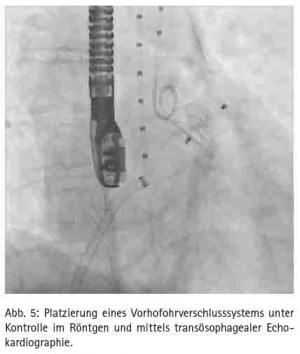

Im Rahmen des Mitra-Clip™-Verfahrens wird ein spezielles Kathetersystem über eine Leistenvene eingebracht und nach transseptaler Punktion kann der Mitra-Clip entsprechend in der maximalen Insuffizienz unter simultaner transösophagealer 3D-EchoKontrolle platziert werden (Abb. 4). Der Eingriff wird in Vollnarkose durchgeführt. Eine Sternotomie oder der Einsatz einer Herz-Lungen-Maschine ist nicht erforderlich. Sollte es dennoch einmal zu einer Notfallsituation kommen, ist ein sofortiges herzchirurgisches Eingreifen jederzeit möglich.